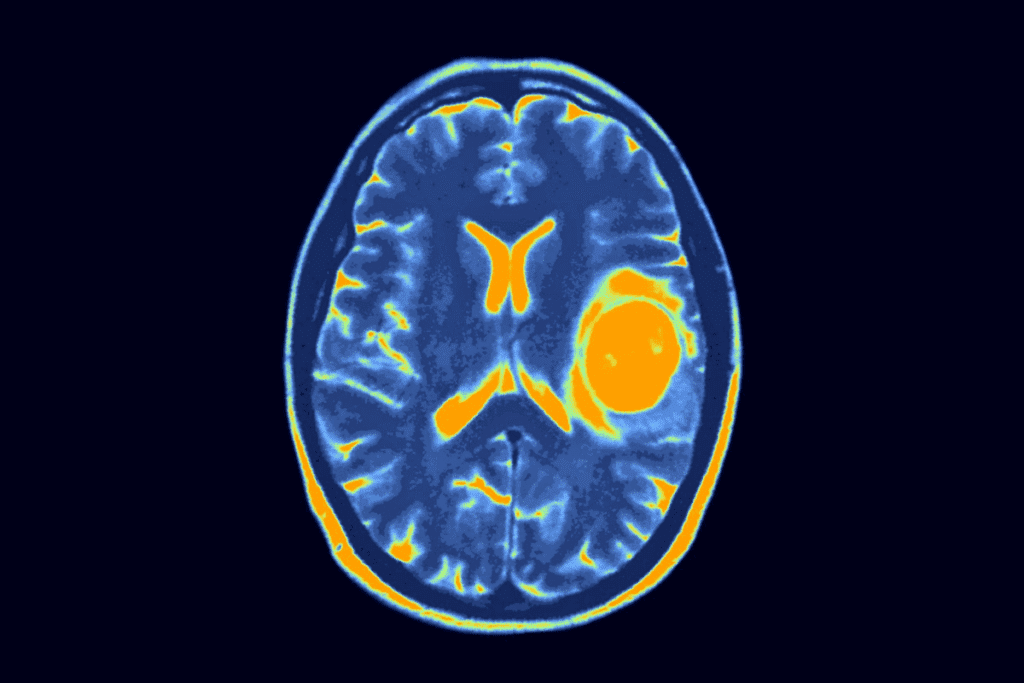

Imaging Tests

Imaging tests are very important for diagnosing brain tumors in kids. The main tests are:

- Magnetic Resonance Imaging (MRI)

- Computed Tomography (CT) scans

- Positron Emission Tomography (PET) scans

These tests help doctors see the tumor, its size, and where it is. They also check how it affects the brain around it.